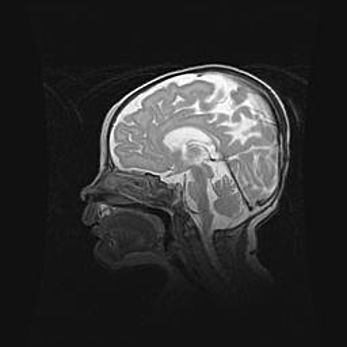

Наружная гидроцефалия с возможной атрофией височных областей.

Возраст: 28 дней

Вес: 3670 г

Пол: мужской

Окружность головы: 38 см

Срок гестации: 40 недель

Гидроцефалия головного мозга у новорожденных – это заболевание, которое характеризуется скоплением избыточного количества спинномозговой жидкости в желудочковой системе головного мозга в результате затруднения её перемещения от места выработки к месту поглощения в кровеносную систему или вследствие нарушения абсорбции. При открытой наружной форме гидроцефалии у новорожденных расширяются и переполняются субарахноидные пространства.

При нормотензивных  формах,  которые,  как  правило,  являются  следствием  перенесенных ишемических  повреждений  паренхимы  мозга,  возможно  сочетание микроцефалии  с нормотензивной гидроцефалией. В основе данных изменений лежит атрофия больших полушарий с преимущественной  локализацией  в  лобно-височных  областях.